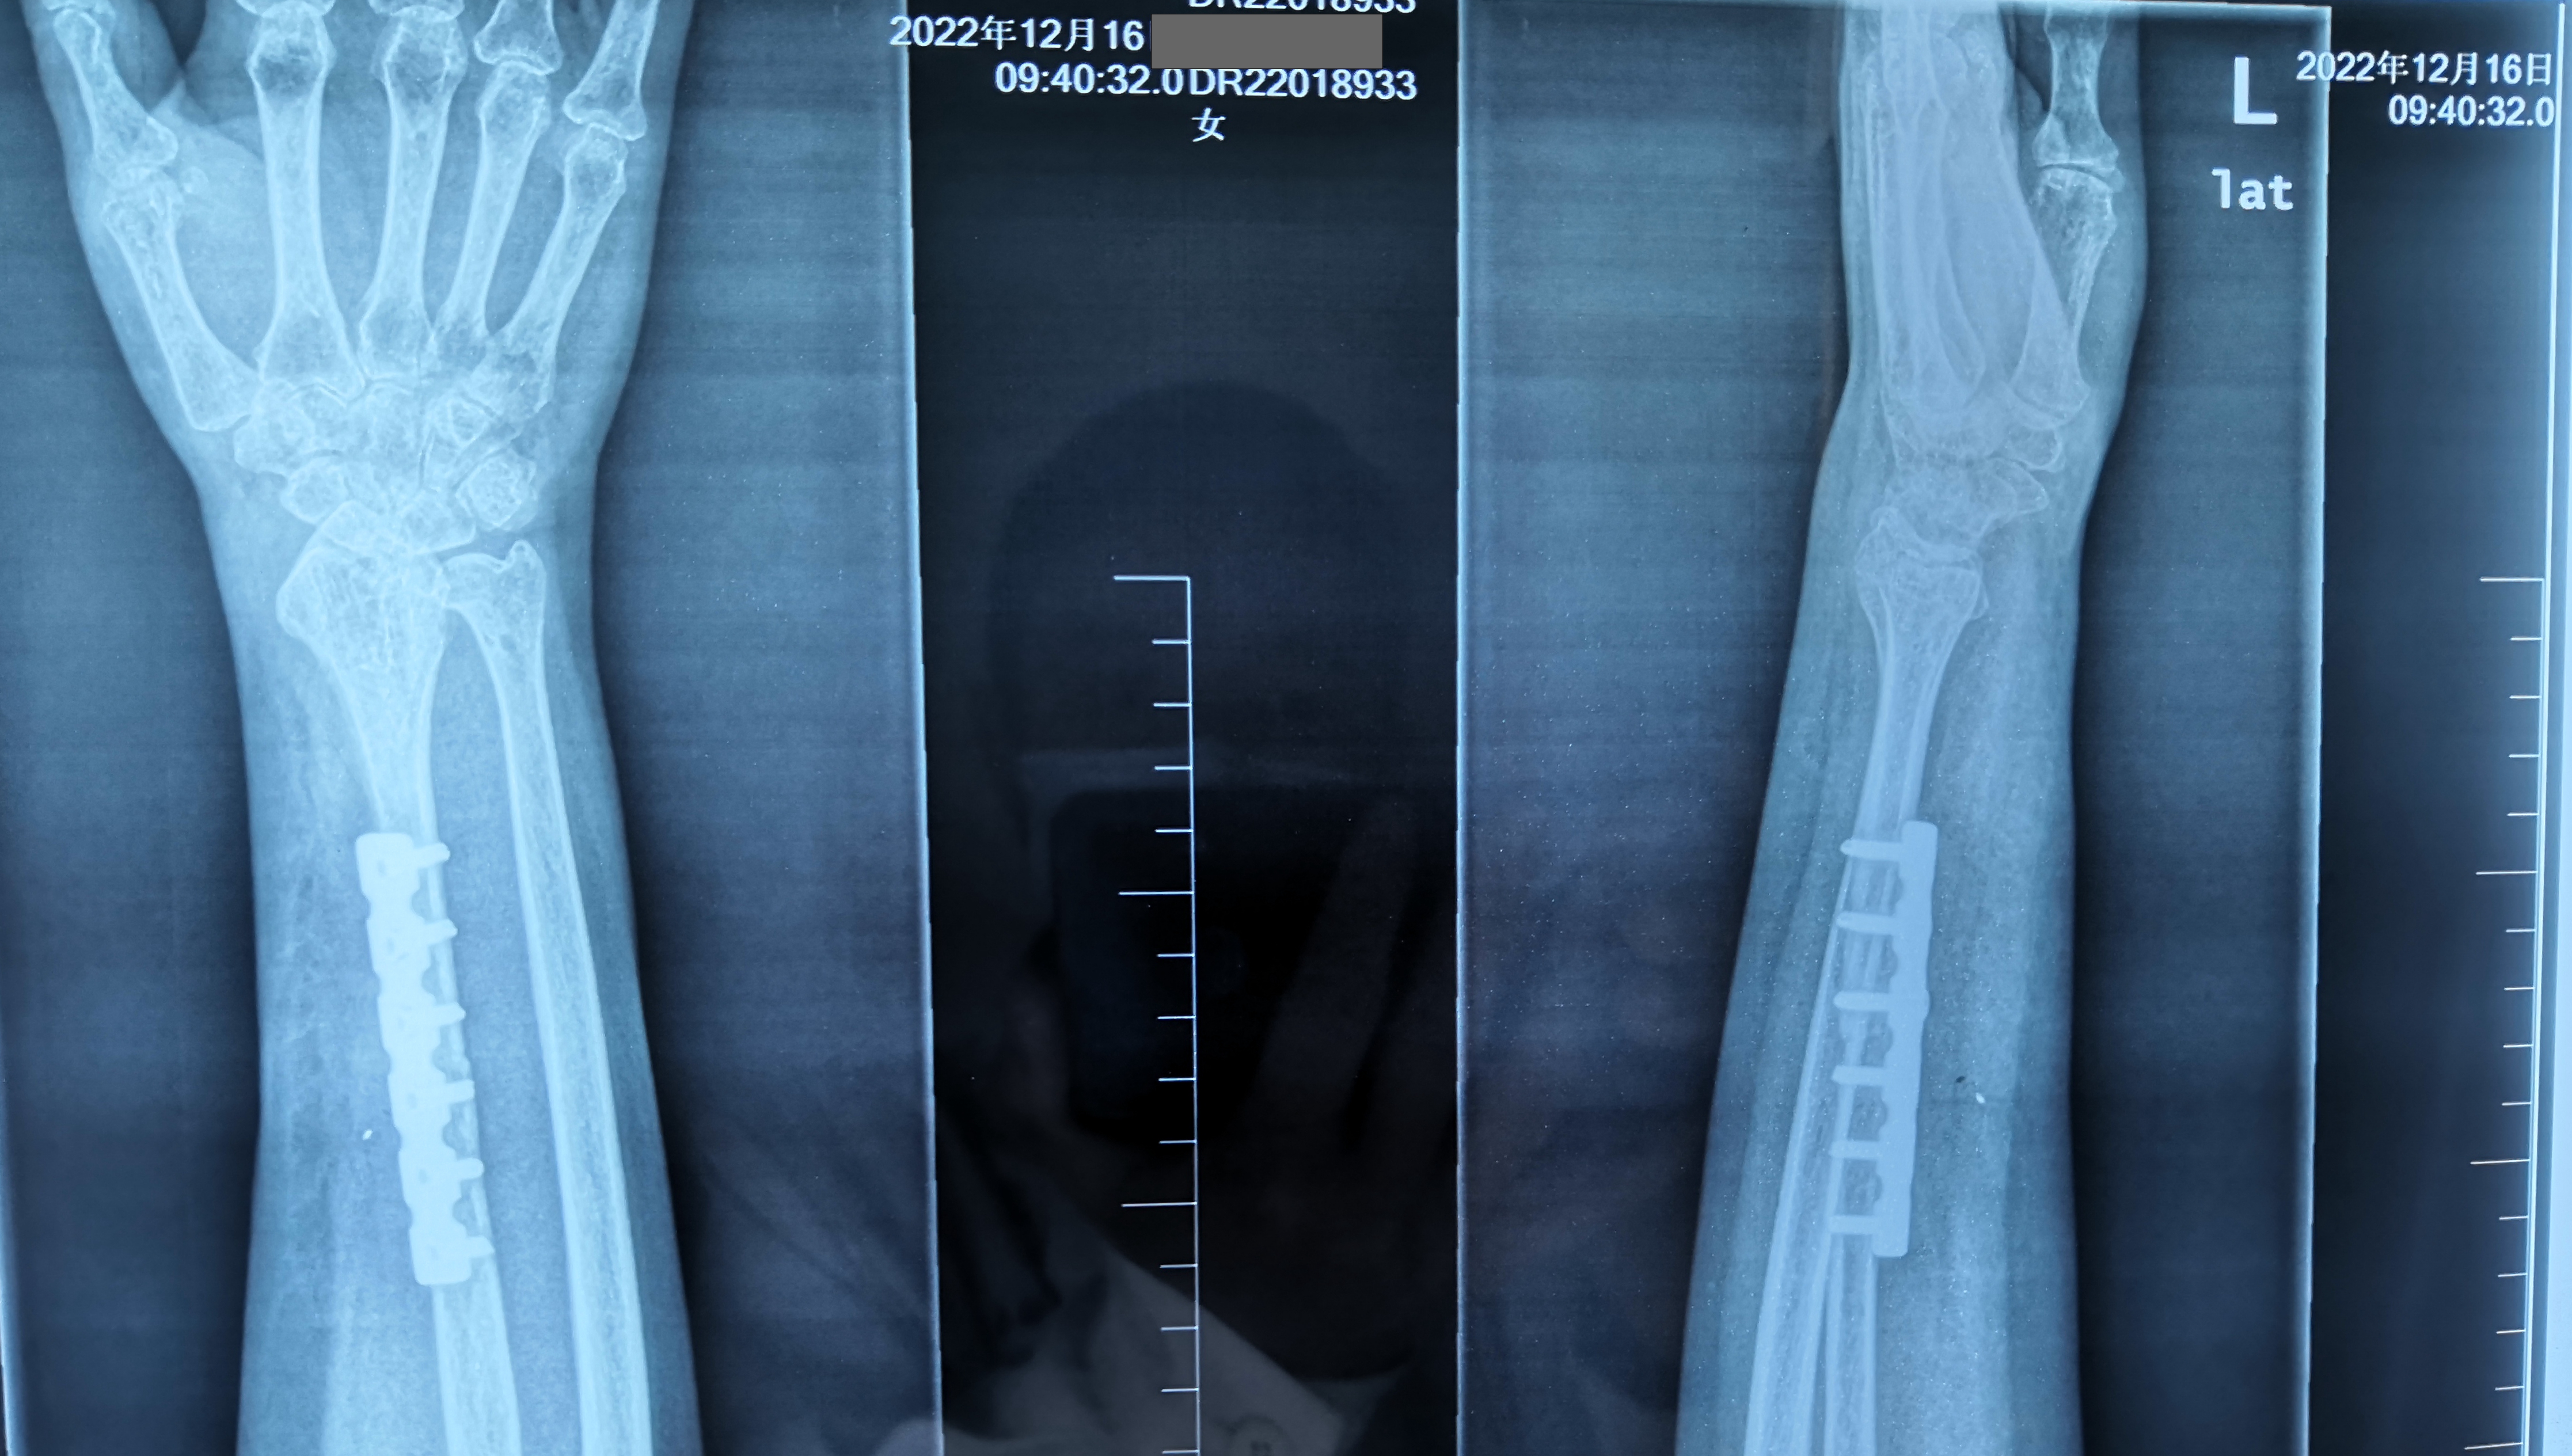

官常和醫(yī)生和他的顯微外科手術(shù)團(tuán)隊(duì)經(jīng)過充分的術(shù)前準(zhǔn)備后,成功為患者順利的進(jìn)行了左側(cè)橈骨下段瘤段切除加游離對側(cè)帶血管蒂腓骨移植重建腕關(guān)節(jié)術(shù)。

術(shù)后3個月,患者手術(shù)的小腿、前臂功能逐漸恢復(fù),影像檢查一切正常,手術(shù)成功?;颊吆图覍偬氐厮蛠礤\旗表示感謝。